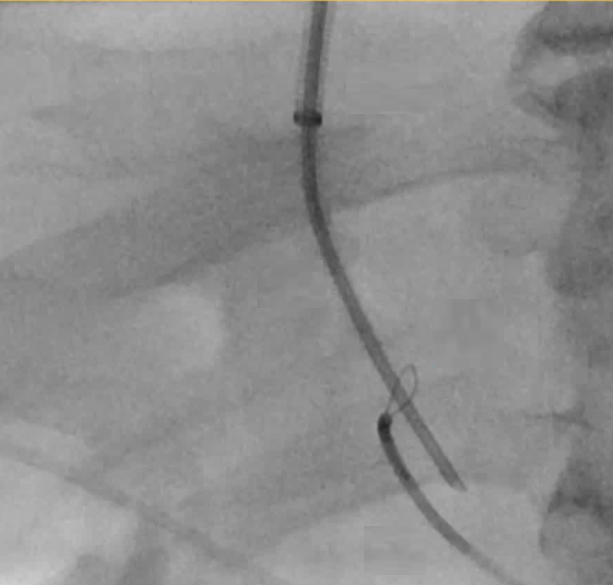

成功实现了经肝通路对门静脉系统的接入,但该接入方式显示出的是一个迂曲的肝周静脉网,且没有合适的肝内门静脉靶点用于进行经颈静脉肝内门体分流术(TIPS)的置入。因此,决定寻找其他途径接入门静脉系统,以便在 TIPS 术前进行再通处理。 通过有限的脐上剖腹探查术,在直视下对肠系膜上静脉的一个分支进行了插管,从而能够置入一个 6 号规格的鞘管。 随后通过该通道实现了对中央/肝内门静脉的直接再通。接着,从肝门静脉窦通道取出一个套管,将其置入肝内门静脉系统,从而能够从中肝静脉进行穿刺操作。 凭借这一通道,椎间盘源性疼痛的手术置入操作得以顺利完成。 患者开始使用克赛(lovenox),并在手术后 3 天出院。 该患者无需再次进行腹腔穿刺,但在经颈静脉肝内门体分流术(TIPS)术后 2.5 个月,因中再次央门静脉狭窄接受了 TIPS 血管成形术并置入了中央支架延伸段。 此病例展示了在慢性中央门静脉血栓形成等复杂情况下通往门静脉系统的其他通路,从而能够进行经颈静脉肝内门体分流术(TIPS)的实施,并对门静脉高压症进行治疗。 1) 传统的门静脉通路方法包括经颈静脉、经皮经肝以及经皮穿刺脾内通路等。 2)若经颈静脉、经肝和经脾的通路均无法使用,则可考虑采用经肠系膜静脉通路进行操作。 3)在腹腔镜手术辅助下或开腹SMV穿刺术,是一种适用于慢性门静脉再通手术的、安全的门静脉穿刺方法。 除了开腹肠系膜静脉或腹腔镜下肠系膜静脉穿刺,也有作者探讨经皮超声引导下穿刺的安全性